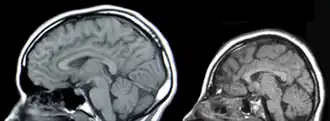

![]() Сравнение МРТ здорового человека (слева) и микроцефала с мутацией гена ASPM | |

![Сравнение МРТ здорового человека (слева) и микроцефала с мутацией гена ASPM[англ.]](./Microcephaly.png)